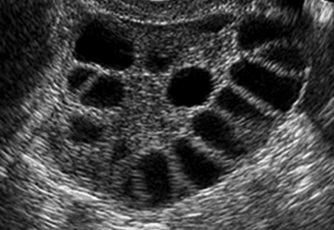

Polycystic Ovary Syndrome (PCOS)

This is the most common cause for ovulation problems in the young. There can be a mixture of symptoms including irregular periods, acne and unwanted extra hair growth. The ovaries with PCOS can often have a very typical appearance on ultrasound.

For reasons that we still do not completely understand, some of the follicles that contain eggs get stuck in the natural process of turnover and form ‘cysts’ seen on ultrasound scanning. This in turn means an egg does not grow enough to be released.

- Polycystic Ovary: An ovary that has at least 12 small ‘cysts’ (follicles) on ultrasound scan.

- Polycystic Ovary Syndrome: A combination of symptoms that may include irregular periods, androgenic symptoms (acne or unwanted hair growth and ultrasound features of a polycystic ovary).